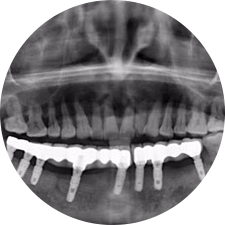

口腔種植是將人工牙根通過(guò)手術(shù)植入牙骨內(nèi),獲得牙槽骨牢固的支持,通過(guò)特殊的裝置和方式連接牙修復(fù)體,獲得與天然牙功能、結(jié)構(gòu)以及美觀(guān)相似的效果。

河北惟德口腔醫(yī)院擁有國(guó)內(nèi)豐富的半口/全口、即刻負(fù)重種植案例,十八年案例跟蹤分析,總結(jié)梳理出的各種不同類(lèi)型的種植案例,Nobel種植體系針對(duì)半口/全口缺牙患者,通過(guò)4-8顆種植體可快速達(dá)到牙齒重建,不僅植入種植體較少,節(jié)省費(fèi)用,手術(shù)時(shí)間更短。

術(shù)前患者CBCT口掃1:1三維重建,模擬手術(shù)過(guò)程及預(yù)測(cè)術(shù)后治療效果,確定每顆植體植入的適合的種植位點(diǎn)、深度及角度,有效避免損傷頜骨重要解剖結(jié)構(gòu),提高手術(shù)準(zhǔn)確度與安全性。

Noble口腔種植體系基本不受年齡限制,適用于缺牙修復(fù),也適用于牙槽骨萎縮、骨質(zhì)疏松、高血壓、糖尿病、超高齡的患者,即種即用,只需少量微小種植體,便可輕松微痛快速重建全口咬合,特殊力學(xué)設(shè)計(jì),針對(duì)許多年紀(jì)較大,骨質(zhì)條件差,身體耐受力差的缺牙老人也能完成“即種即用”,受到廣泛好評(píng)。

惟德口腔種植體系是以患者感受為中心,取代傳統(tǒng)種植牙手術(shù)需要翻瓣、打孔、縫合,術(shù)前、術(shù)中、術(shù)后的繁復(fù)流程,采用3D導(dǎo)航微創(chuàng)準(zhǔn)確種植技術(shù),通過(guò)數(shù)字化CAD/CAM掃描技術(shù)獲得缺牙患者口腔數(shù)據(jù),以數(shù)據(jù)為基礎(chǔ)重建口腔模型進(jìn)行模擬種植。

術(shù)前將患者口內(nèi)的CBCT數(shù)據(jù)及咬合關(guān)系上傳到計(jì)算機(jī)中,建立1:1三維重建,模擬手術(shù)過(guò)程及預(yù)測(cè)術(shù)后治療效果,找出較佳種植位點(diǎn)、深度及角度,獲取實(shí)際種植體在頜骨內(nèi)的具體三維位置,有效避免損傷頜骨重要解剖結(jié)構(gòu),大大降低手術(shù)風(fēng)險(xiǎn),提升種植成功率。